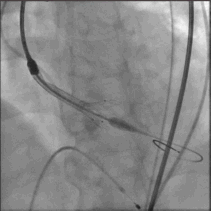

球囊预扩

大小球囊依次预扩

输送系统到位

圈套器snare 协助输送系统安全准确达到预计区域,猪尾主动脉根部造影确认系统和窦底的相对位置,调整重置锚定区